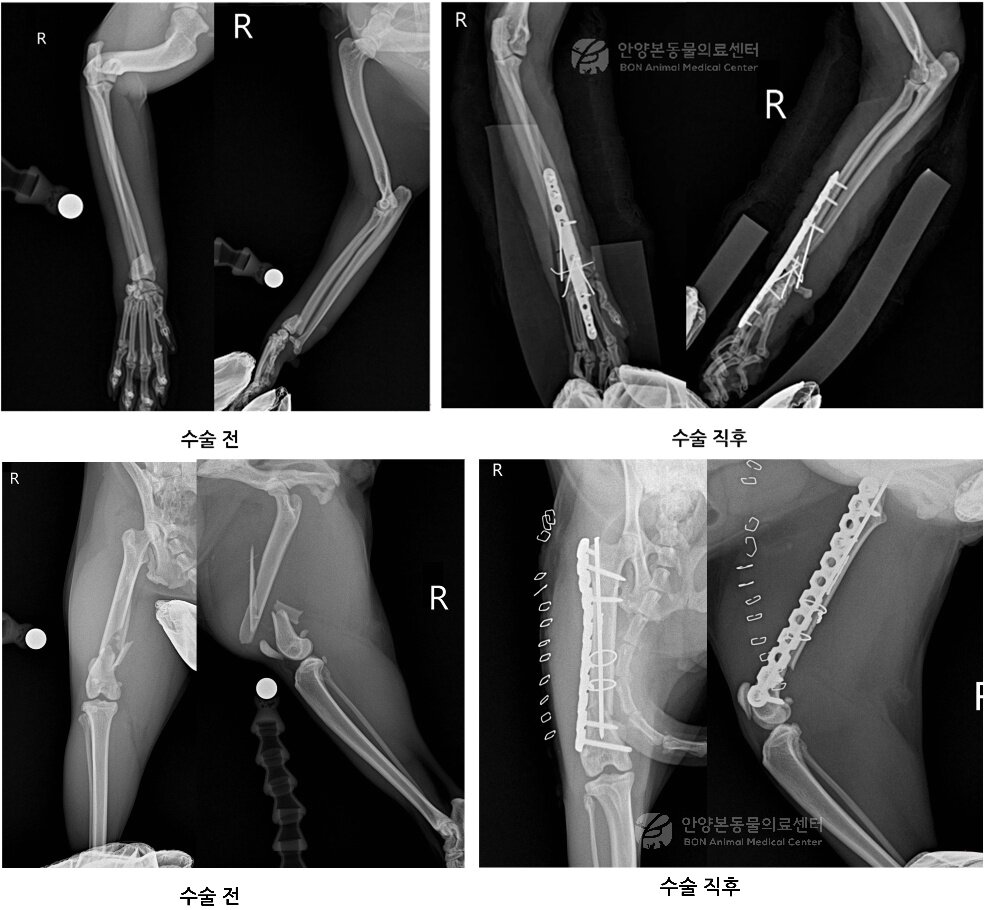

본문 이미지 - 앞다리와 뒷다리 수술 전 후 엑스레이 영상(본동물의료센터 제공) ⓒ 뉴스1

앞다리와 뒷다리 수술 전 후 엑스레이 영상(본동물의료센터 제공) ⓒ 뉴스1